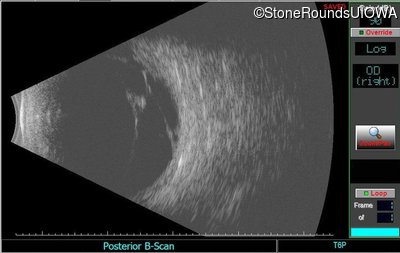

B-Scan Ultrasonography - Left - 20/200 sc

Exemplar